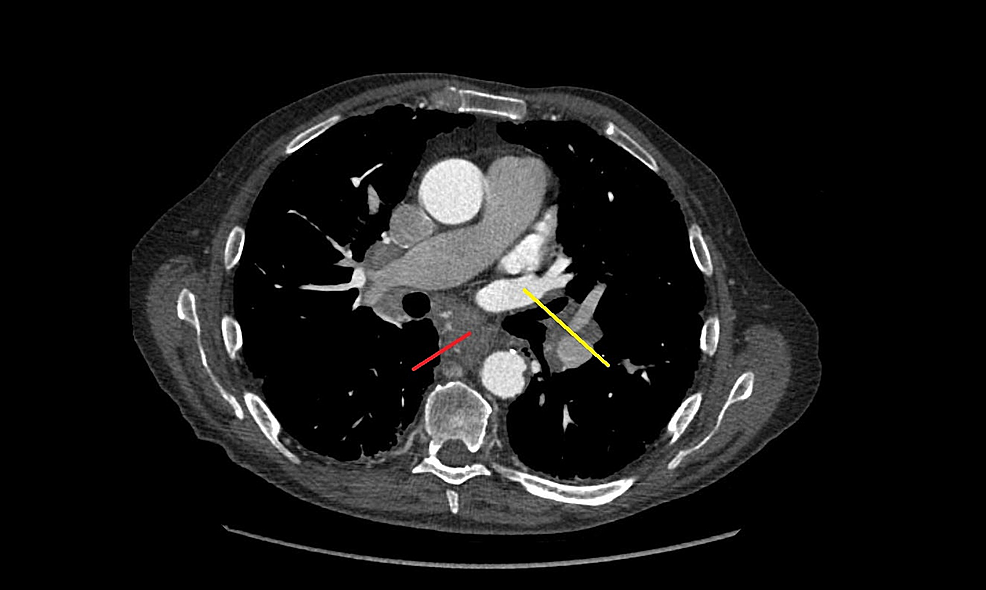

(2) cancer is found in fluid around the lungs or the heart. For less accessible lesions, they may use a more invasive surgical procedure lung cancer is a potentially fatal type of cancer, but people who receive an early diagnosis often have a good chance of survival. Crogvstage iv lung cancer ajcc v6.

Some stage 4 lung cancer patients are cured with surgical removal of the cancer in the lung and then directed treatment against an isolated or limited metastasis.